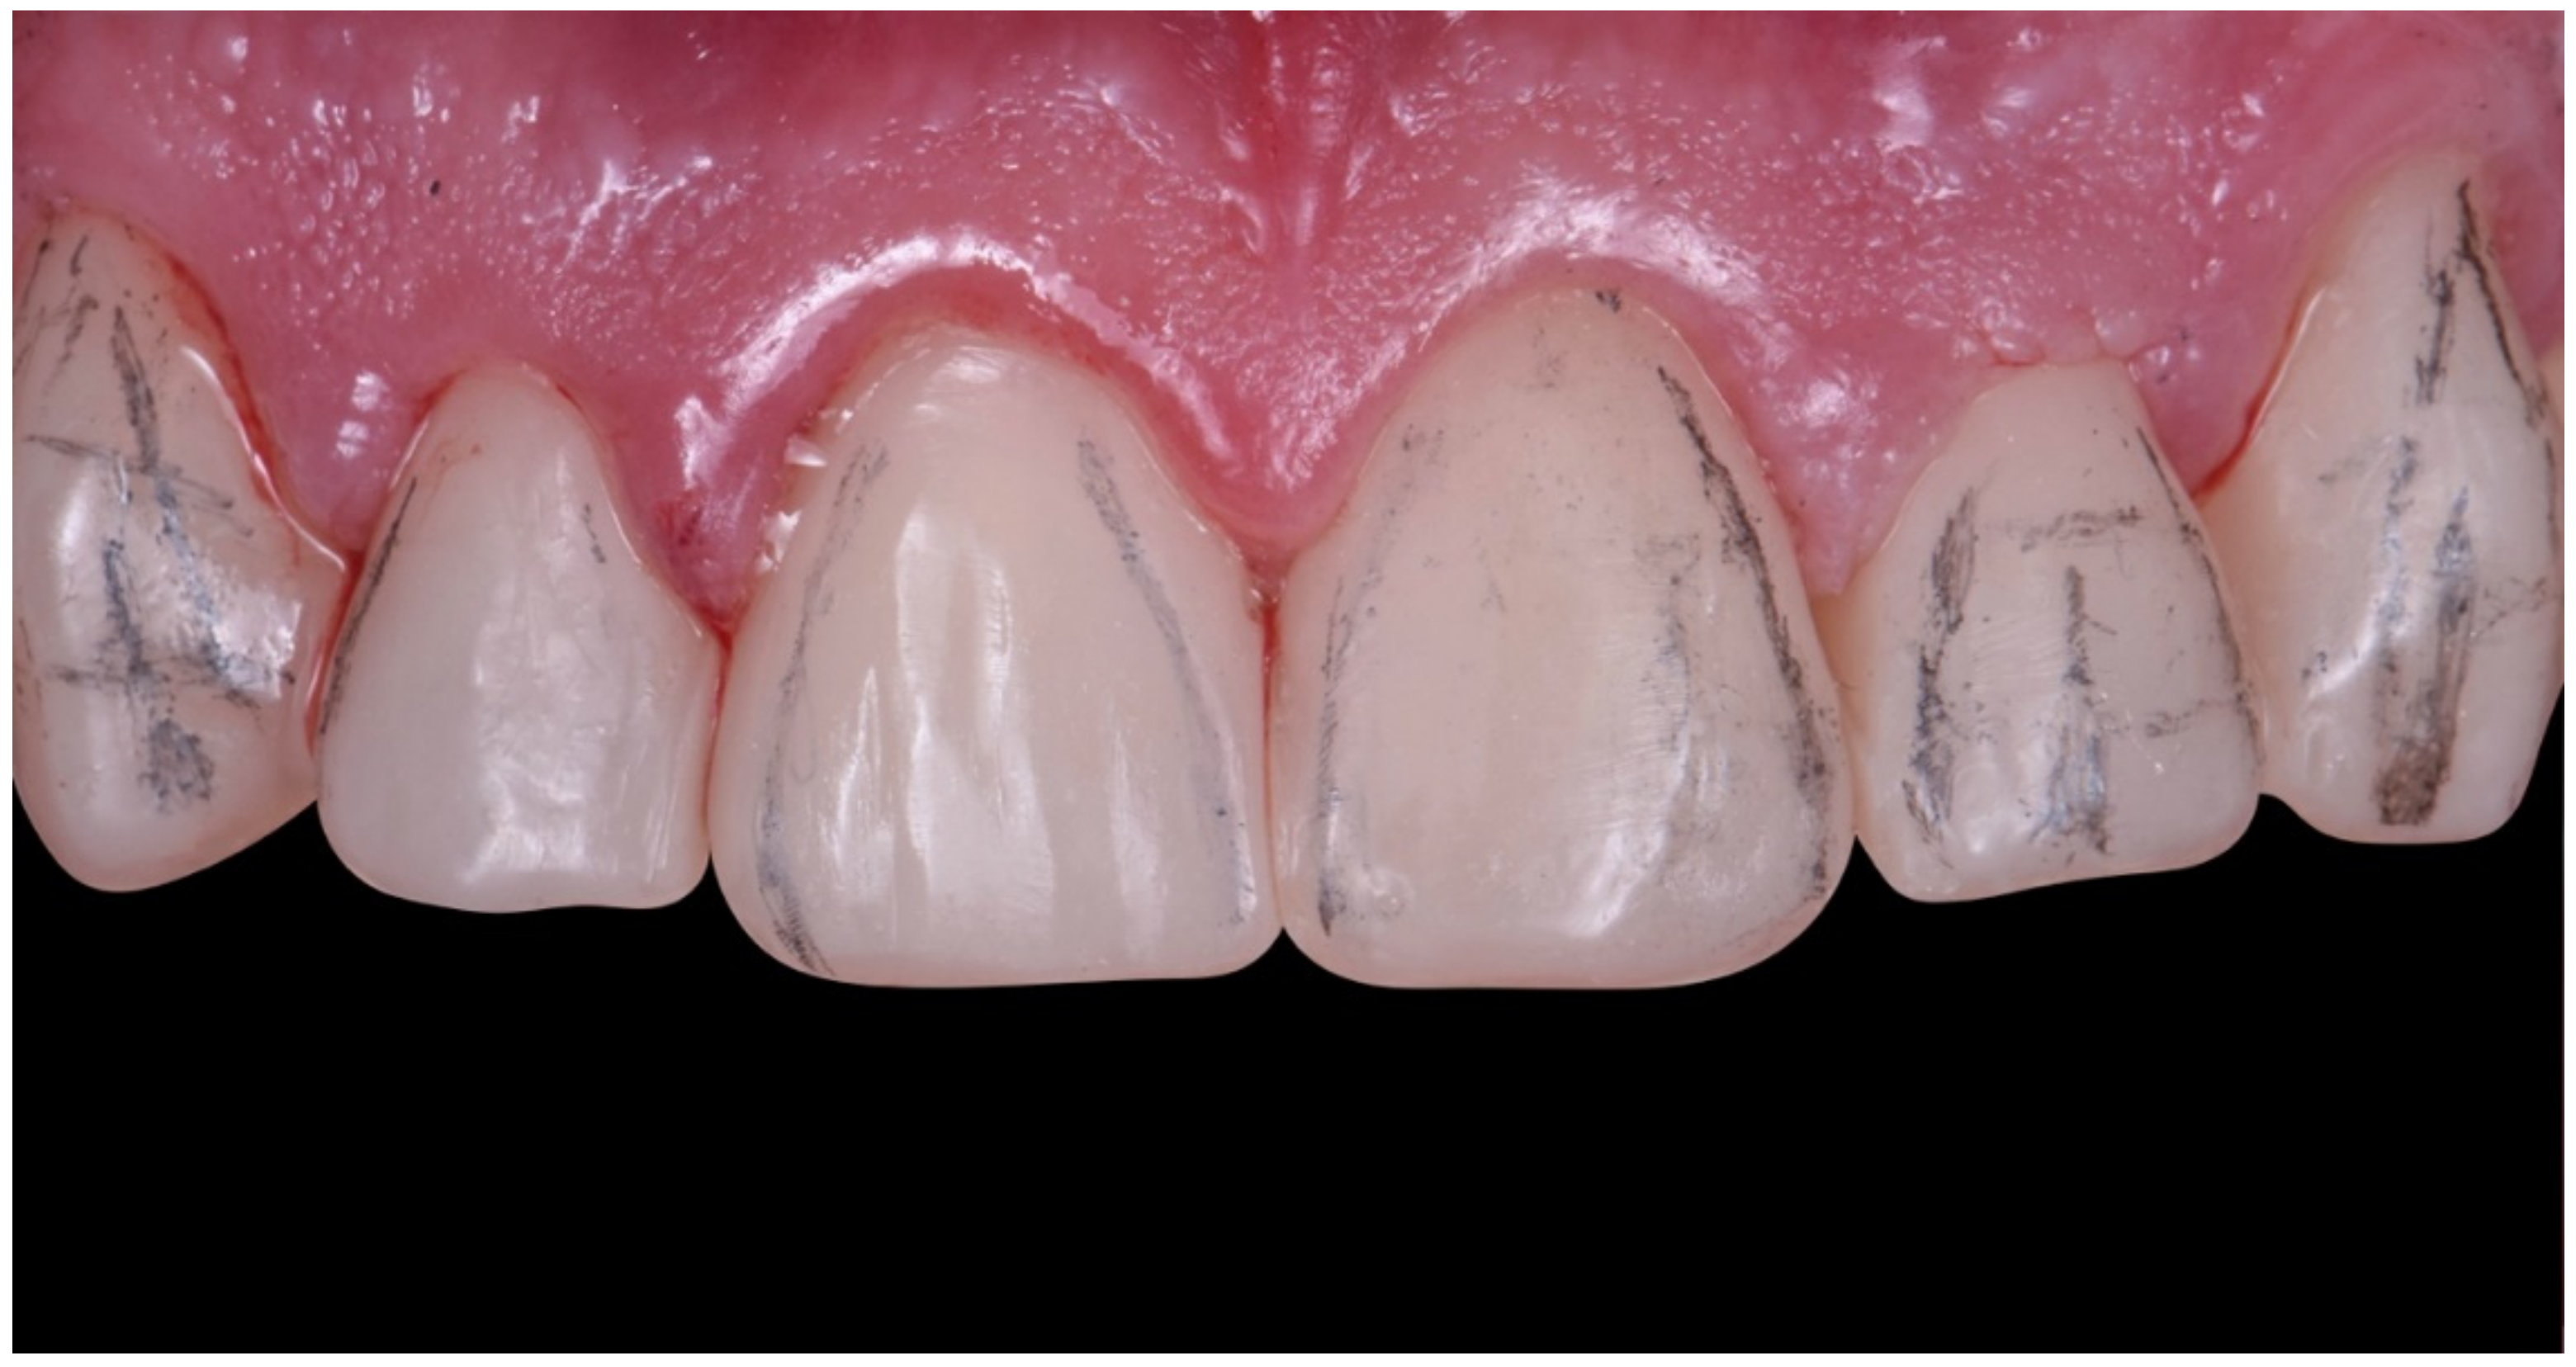

2. Clinical Report

2.1. Planning Phase

2.2. Restorative Phase